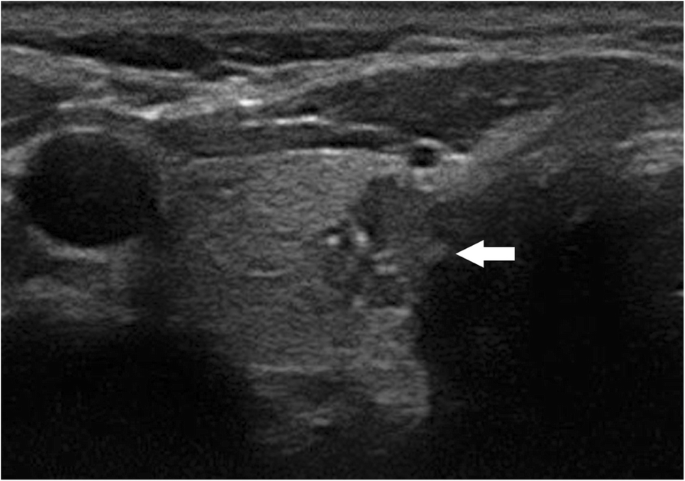

The results of the multivariate logistic regression analysis for US characteristics are summarized in Table 3. The proportion of MTMCs with ovoid to round shapes (Figs. 1 and 2) was higher than that of PTMCs (Fig. 3) (54.35% vs 9.56%, P = 0.007), but PTMCs with taller-than-wide shapes (Figs. 4 and 5) were much more common than MTMCs with the same shape (Fig. 6) (59.56% vs 19.57%, P = 0.000). An unclear boundary seemed to be more commonly detected in PTMCs (Fig. 3) than in MTMCs; however, there was no significant difference (86.03% vs 43.48%, P = 0.188). There were more nodules with a > 50% solid composition in the MTMC group than in the PTMC group (13.04% vs 1.47%, P = 0.032). Calcifications were not commonly observed in either group; when they occurred, macrocalcifications were more often seen in MTMCs (Fig. 2) than in PTMCs (Fig. 3) (21.74% vs 6.62%, P = 0.004). Microcalcifications were more frequently detected in PTMCs (Fig. 4), although there was no significant difference (10.87% vs 29.41%, P = 0.214). Hypervascularity was observed in 58.70% of MTMCs but only in 19.85% of PTMCs (P = 0.000).